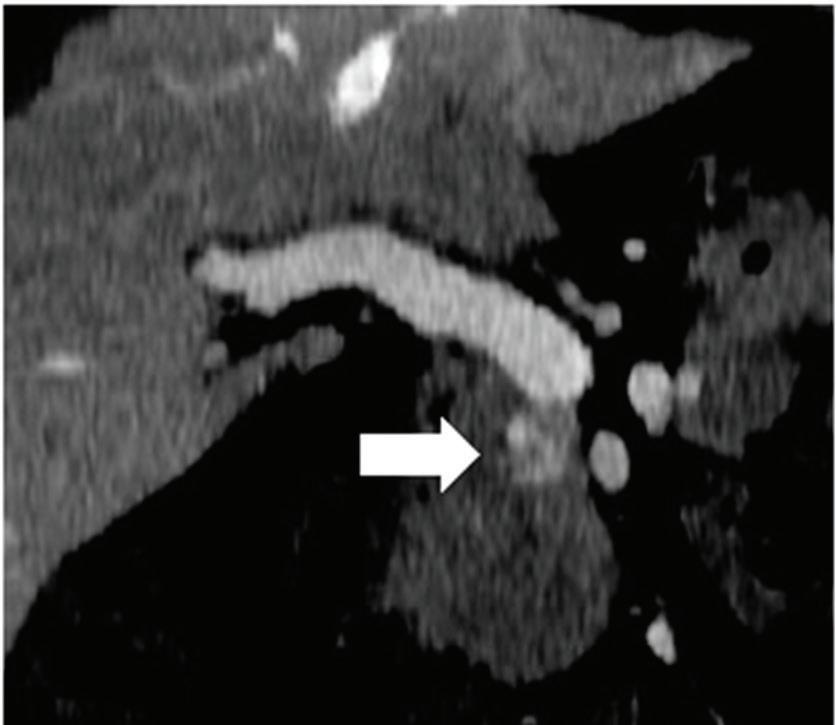

Renal and adrenal gland tumors. Contrast-enhanced-DECT images are particularly useful for the characterization of incidental renal or supra-renal lesions and for their follow-up, without the need of conventional unenhanced acquisition, translating into achieving a 30% mean dose savings for triphasic and up to 50% for biphasic renal protocols in daily clinical practice.17 It is also very useful in depicting hypervascular renal cell carcinoma metastasis in the liver or other sites, such as in the peritoneum and bowel wall (Figures 2 and 3).

Effectiveness of spectral CT imaging for detection of hypervascular liver metastases. A small hypervascular metastasis (arrow) from renal cell carcinoma. (a) Axial contrast-enhanced conventional CT image obtained in the arterial phase, corresponding (b) monoenergetic 50 keV, and (c) Z effective image.

Effectiveness of spectral CT imaging for detection of a peritoneal implant from a renal cell carcinoma invading the bowel wall (arrow). (a) Coronal contrast-enhanced conventional CT image obtained in the arterial phase, corresponding (b) Z effective, (c) monoenergetic 50 keV, and (d) iodine-density image.